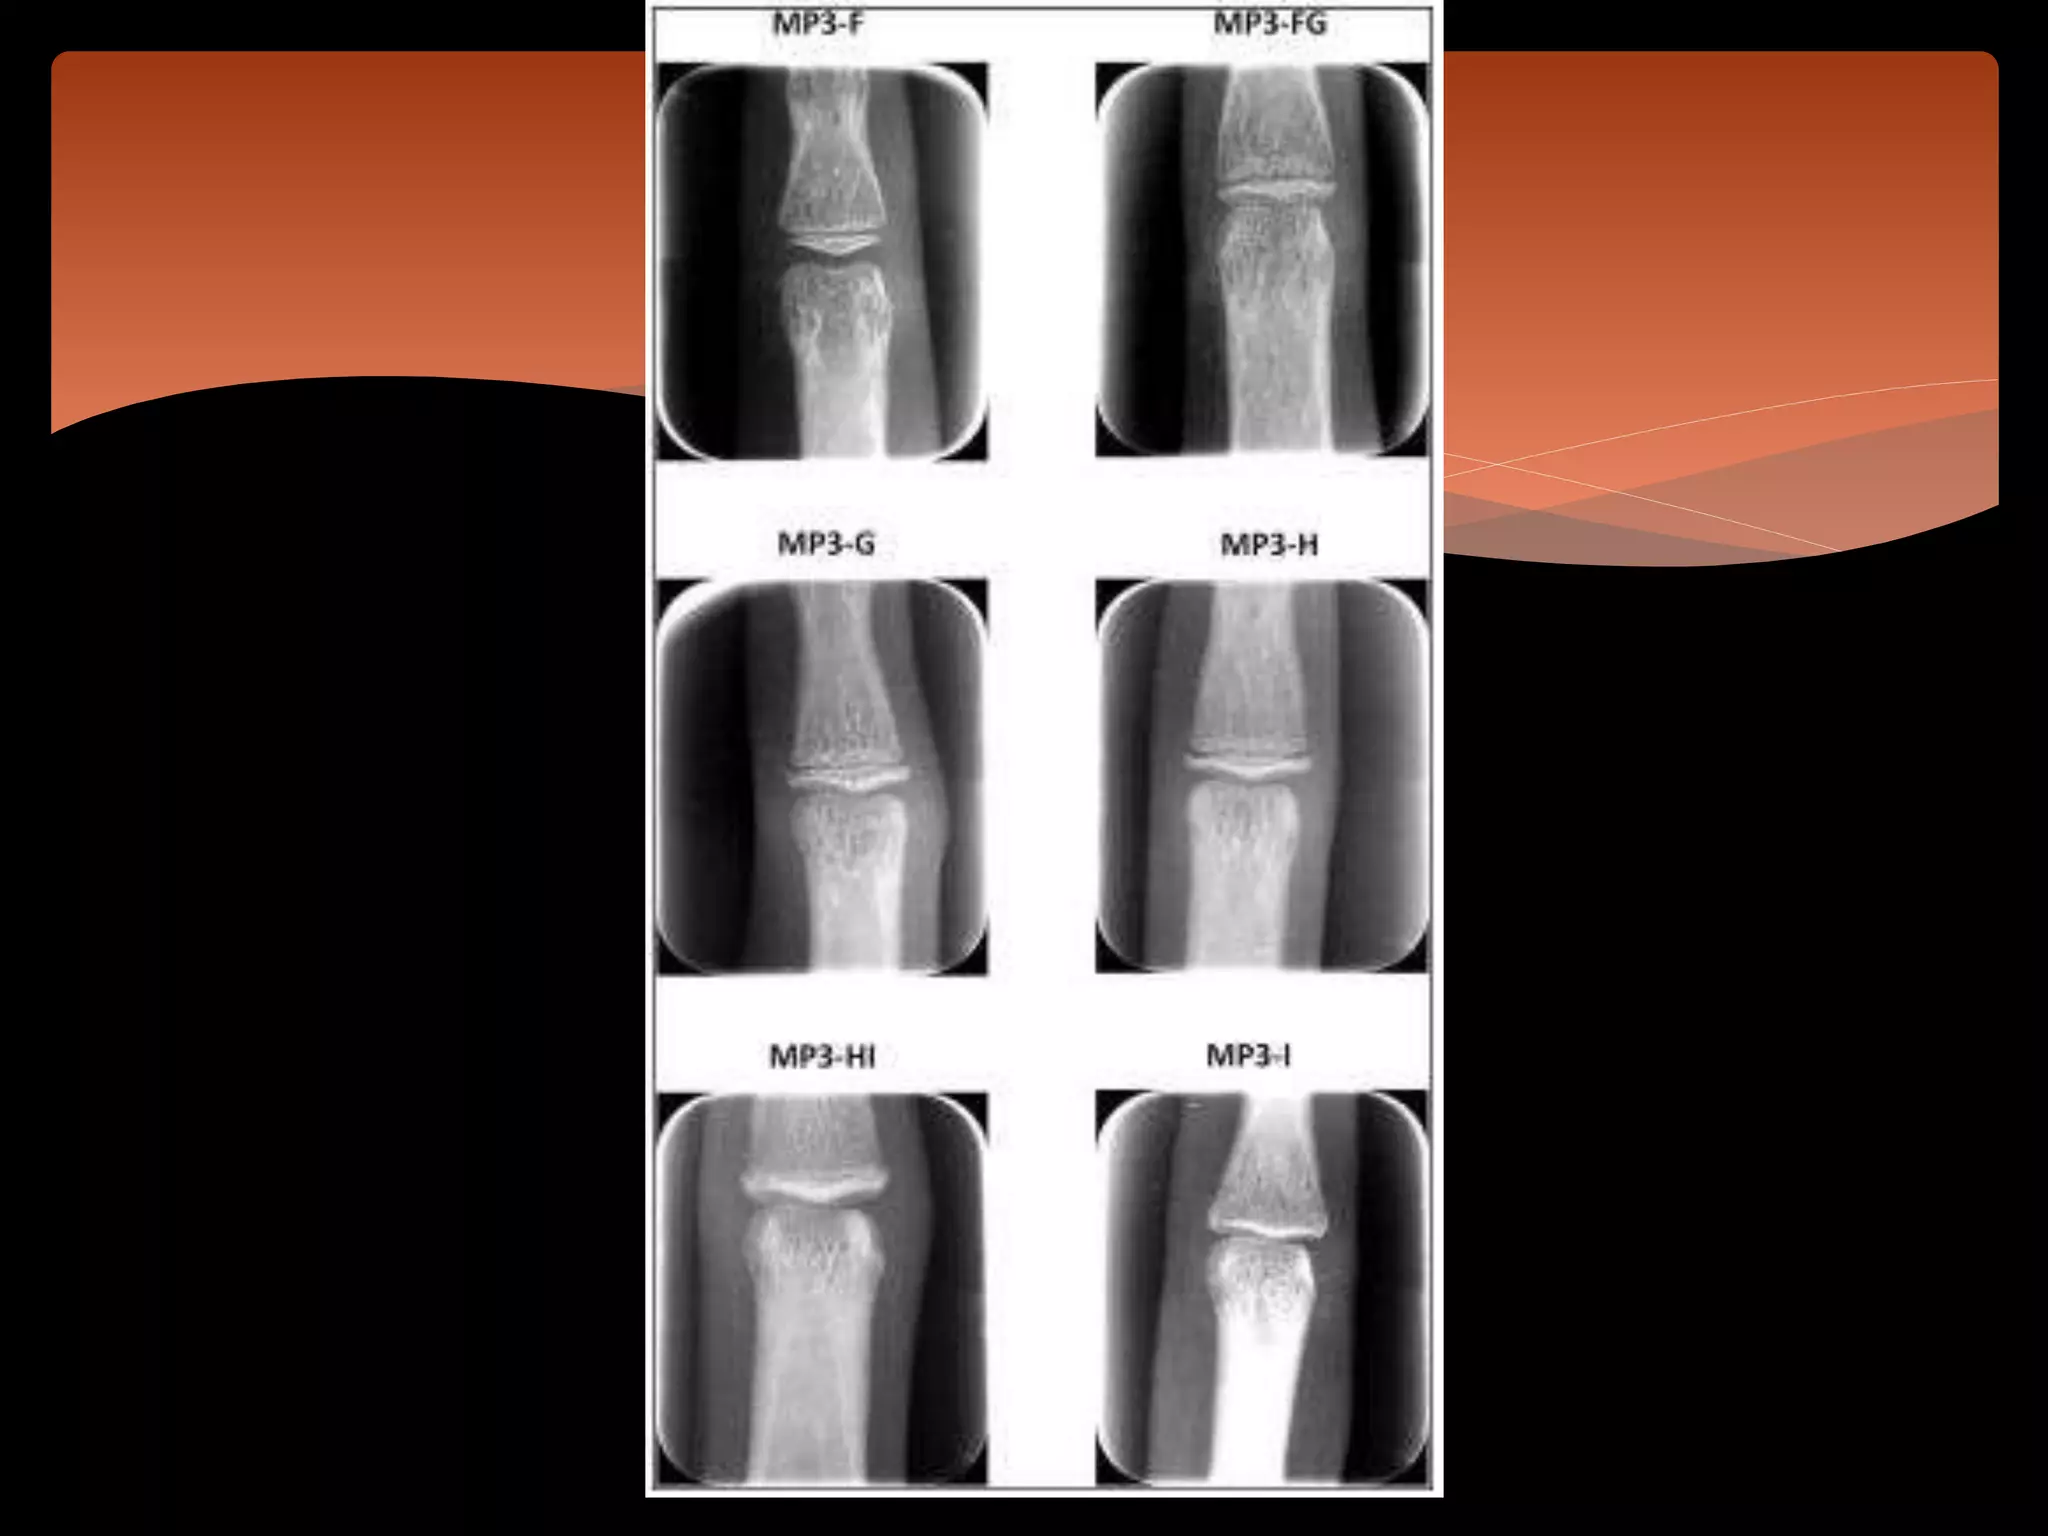

 By Rajagopal et al (2002)

 Additional bone stage between MP3-H and MP3-I,

which is called MP3-HI stage has been added.

Modified Hagg and Taranger

A comparison of modified MP3 stages and the cervical vertebrae as growth

indicators. JCO -2002 Jul;36(7):398-406

Comprises 6 stages,

 1.MP3-F stage is the start of the curve of pubertal growth spurt:

the epiphysisis as wide as the metaphysis

 The ends of the epiphysis are tapered and rounded; the

metaphysis shows no undulation; and the radiolucent gap

(representing the cartilaginous epiphyseal growth plate)

between the epiphysis and the metaphysisis wide

2.MP3-FG stage is the acceleration of the curve of the pubertal

growth spurt: the epiphysisis as wide as the metaphysis

 the metaphysis begins to show as light undulation

 radiolucent gap between the metaphysis and the epiphysisis

wide.

3.MP3-G stage is the maximum point of the pubertal growth

spurt: the sides of the epiphysis have thickened and cap its

metaphysis, forming a sharp distal edge on at least 1side; marked

undulations in the metaphysis give it a “Cupid's bow” appearance.

 The radiolucent gap between the epiphysis and the

metaphysisis moderate.

 4.MP3-H stage is the deceleration of the curve of the pubertal

growth spurt

 fusion of the epiphysis and the metaphysis begins

5.MP3-Hi stage is the maturation of the curve of the pubertal

 The superior surface of the epiphysis has a smooth concavity

 The metaphysis shows a smooth,convex surface

6.MP3-I stage is the end of the pubertal growth spurt

 fusion of the epiphysis and the metaphysis is complete.

 There is no radiolucent gap between the metaphysis and the

epiphysis.